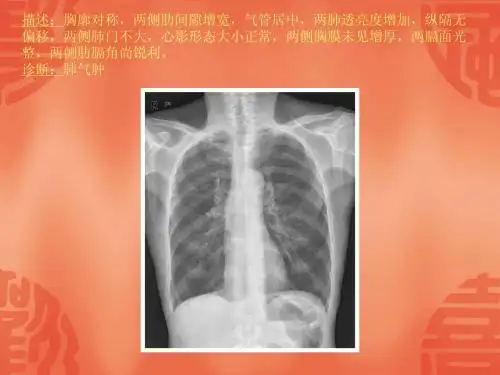

常见40张X片读片及诊断 ppt课件